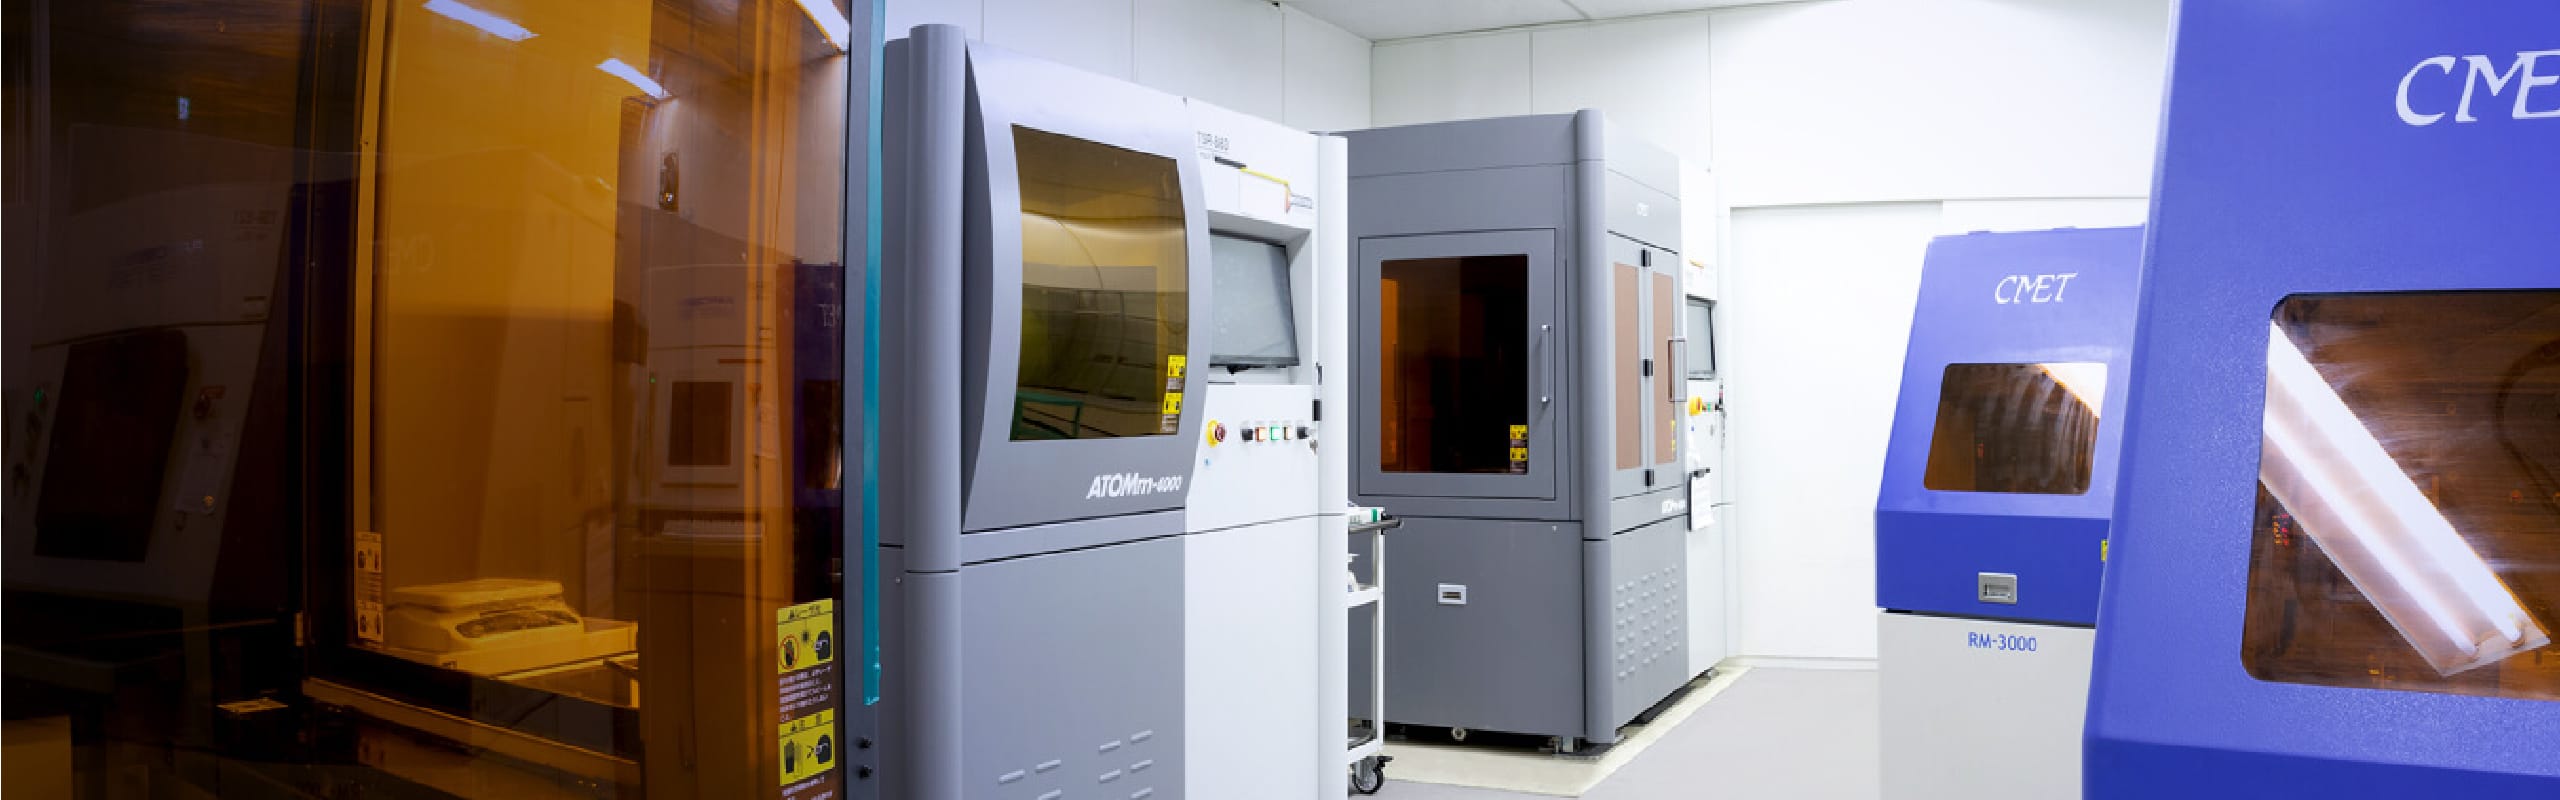

Use of 3D Printers

While most of the models for verification of medical devices used to be made of plaster, in recent years, there has been an increasing demand for soft and transparent models that are closer to the human body. Silicon materials can now reproduce blood vessels, nerves, and cartilage of the nose of the living body, and epoxy light-curing resin materials can be used to make transparent models, so that the inside of the model can be visually checked and the procedure can be confirmed in real time. The bone model can be used not only by medical professionals to confirm procedures and formulate treatment plans through preoperative simulation, but also by medical device manufacturers as a development tool, sales promotion tool, marketing tool, and internal training tool. It can also be used as a development tool for medical device manufacturers, a sales promotion tool, a marketing tool, and an internal training tool.